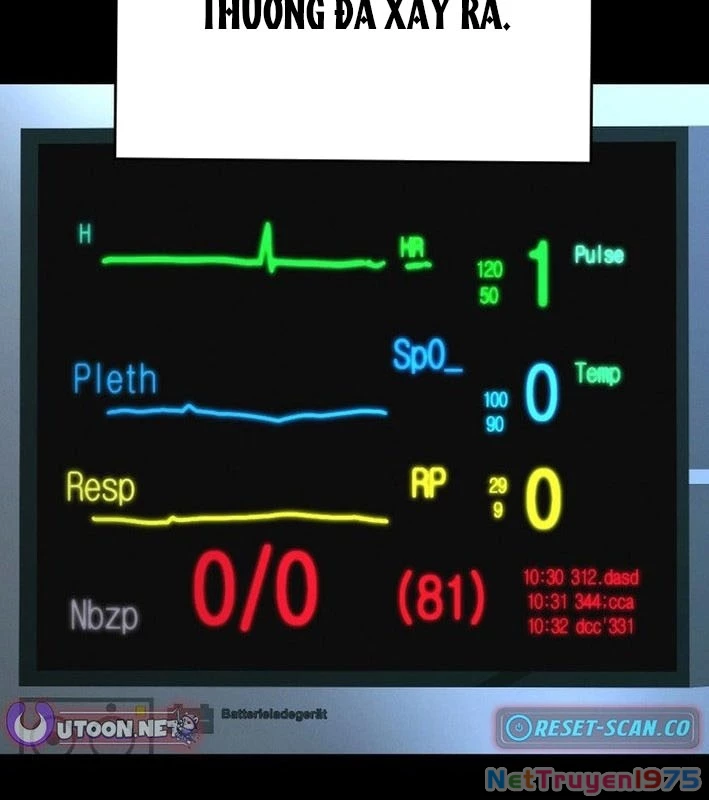

Kẻ Chôn Cất Quái Vật - Chapter 1